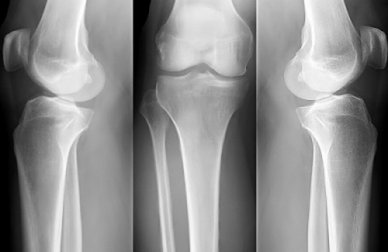

Rimedi casalinghi per l'osteoporosi

Il modo migliore per combattere questo problema di salute sono i rimedi casalinghi per l’osteoporosi. Aiutano a rafforzare le ossa, indipendentemente dall’età.